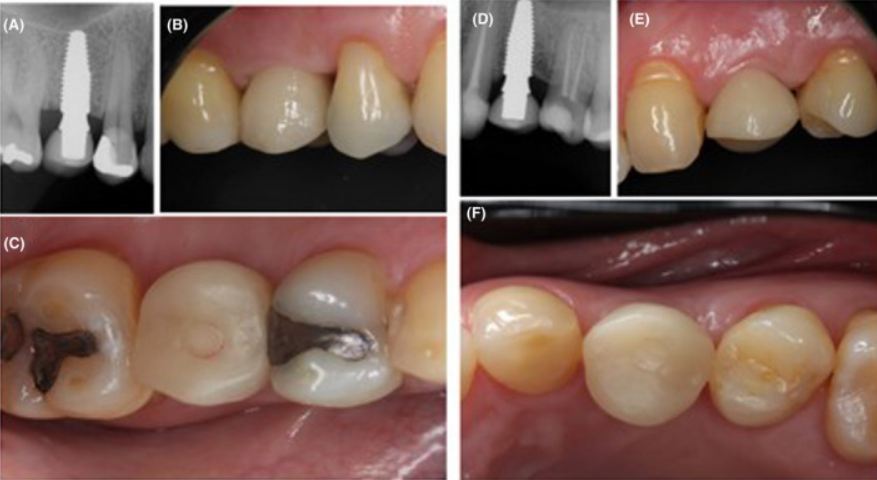

Клінічний випадок: заміщення втрачених 15 і 24 зубів за допомогою імплантатів Neodent Zirconia з подальшим протезуванням.

Встановлені імплантати з негайно виготовленими тимчасовими конструкціями.

Клінічна ситуація на огляді через 12 місяців.